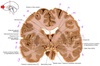

23

Q

a

septum pellucidum

24

b

Body of lateral ventricle

25

c

Corona radiata

26

d

Column of fornix

27

e

Third ventricle

28

f

Anterior commissure

29

g & h

amygdala (nuclear complex)

30

i

globus pallidus internus

31

j

globus pallidus externus

32

k

Putamen

33

L

Internal capsule genu

34

m

head of caudate nucleus

35

n

Anterior tubercle of thalamus

36

o

Body of corpus callosum